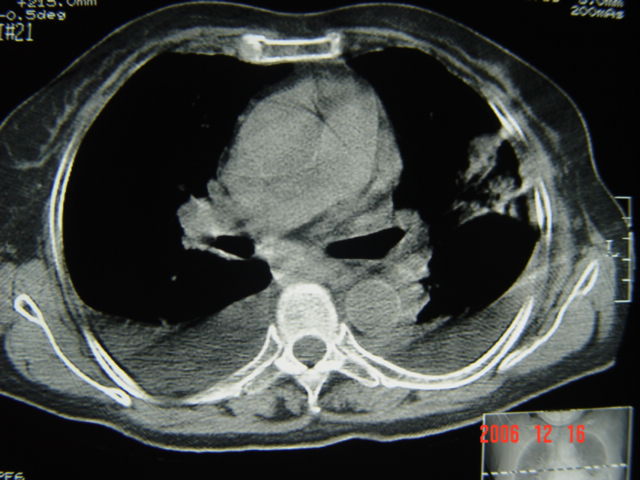

左第八肋腋侧呈膨胀性骨质破坏,内侧见软组织密度肿块。左肺舌段呈楔形实变,基底近胸壁,尖端向肺门。双侧胸壁后缘见新月形水样密度区。

考虑:1、左第8肋骨转移瘤;

2、左肺舌叶肺栓塞可能性大;

3、双侧中量胸腔积液。

考虑:1、左第8肋骨转移瘤;恶性间皮瘤?